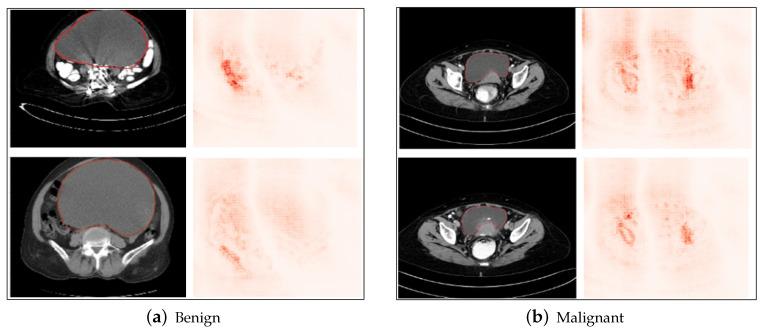

Deep learning architectures like ResNet and Inception have produced accurate predictions for classifying benign and malignant tumors in the healthcare domain. This enables healthcare institutions to make data-driven decisions and potentially enable early detection of malignancy by employing computer-vision-based deep learning algorithms. These CNN algorithms, in addition to requiring huge amounts of data, can identify higher- and lower-level features that are significant while classifying tumors into benign or malignant. However, the existing literature is limited in terms of the explainability of the resultant classification, and identifying the exact features that are of importance, which is essential in the decision-making process for healthcare practitioners. Thus, the motivation of this work is to implement a custom classifier on the ovarian tumor dataset, which exhibits high classification performance and subsequently interpret the classification results qualitatively, using various Explainable AI methods, to identify which pixels or regions of interest are given highest importance by the model for classification. The dataset comprises CT scanned images of ovarian tumors taken from to the axial, saggital and coronal planes. State-of-the-art architectures, including a modified ResNet50 derived from the standard pre-trained ResNet50, are implemented in the paper. When compared to the existing state-of-the-art techniques, the proposed modified ResNet50 exhibited a classification accuracy of 97.5 % on the test dataset without increasing the the complexity of the architecture. The results then were carried for interpretation using several explainable AI techniques. The results show that the shape and localized nature of the tumors play important roles for qualitatively determining the ability of the tumor to metastasize and thereafter to be classified as benign or malignant.

像ResNet和Inception这样的深度学习架构在医疗保健领域对良性和恶性肿瘤的分类中产生了准确的预测。这使医疗机构能够做出数据驱动的决策,并有可能通过采用基于计算机视觉的深度学习算法实现恶性肿瘤的早期检测。这些卷积神经网络(CNN)算法除了需要大量数据外,在将肿瘤分类为良性或恶性时,还能识别出重要的高层和低层特征。然而,现有文献在所得分类的可解释性方面有限,并且难以确定哪些确切特征是重要的,而这在医疗从业者的决策过程中至关重要。因此,这项工作的动机是在卵巢肿瘤数据集上实现一个定制分类器,该分类器具有高分类性能,随后使用各种可解释人工智能方法对分类结果进行定性解释,以确定模型在分类时赋予哪些像素或感兴趣区域最高的重要性。该数据集包括从轴向、矢状面和冠状面获取的卵巢肿瘤CT扫描图像。本文实现了包括从标准预训练的ResNet50派生而来的改进版ResNet50在内的先进架构。与现有先进技术相比,所提出的改进版ResNet50在测试数据集上表现出97.5%的分类准确率,且没有增加架构的复杂性。然后使用几种可解释人工智能技术对结果进行解释。结果表明,肿瘤的形状和局部特征在定性确定肿瘤转移能力从而将其分类为良性或恶性方面起着重要作用。